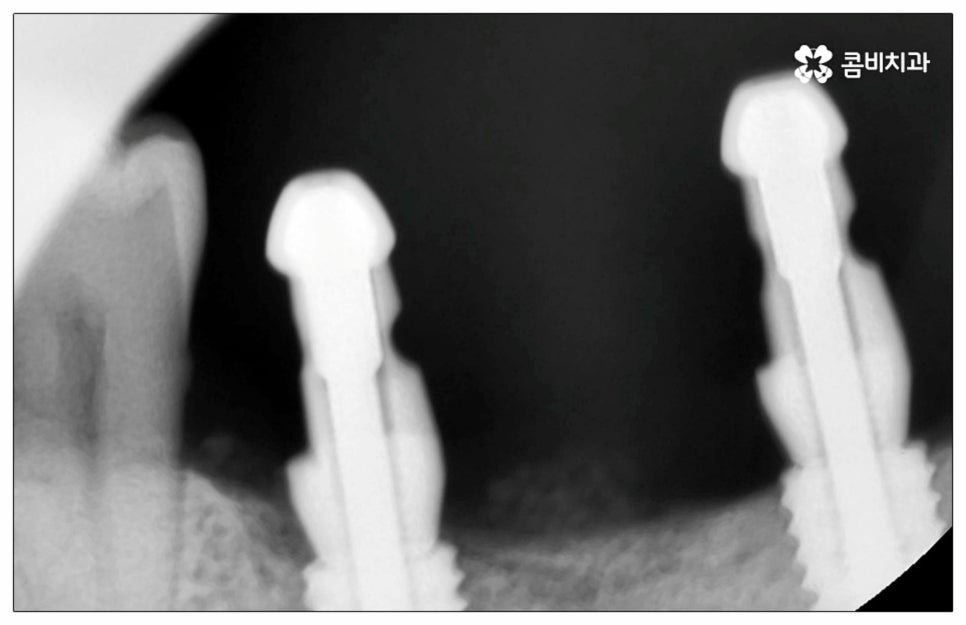

예전에는 이런 상황에서 틀니를 많이 이용하였으나 저작력 회복이 본래 자신의 치아 대비 20~30% 정도 밖에 되지 않고 잦은 탈락 위험 및 이물감, 잇몸을 눌러 장기적으로 잇몸뼈가 내려앉을 수 있다는 점 등 여러 가지 불편함이 있어 요즘은 임플란트 시술을 선호하시는 분들이 더 많아지고 있어요. 임플란트란 인체에 무해하며 잇몸뼈와 잘 결합하는 인공 치근을 잇몸뼈에 직접 식립하고 그 위로 기둥이 되는 중간 지대주와 치아 머리가 되는 크라운 보철물을 연결하여 인공 치아를 만들어 주는 시술을 말하는데, 자연 치아의 80% 정도 저작력 회복이 가능하기 때문에 식사를 할 때 음식을 크게 가리지 않아도 된다는 점 그리고 심미적으로 봤을 때 주변 치아와 자연스럽게 어우러진다는 점 때문에 각광을 받고 있습니다. 게다가 건강 보험 가입자이면서 만 65세 이상 부분 무치악 환자라면 평생 임플란트 2개까지 보험 적용을 받아 비용 부담을 줄일 수 있기 때문에 더욱 더 수요가 늘어나 이제는 치아 상실에 대체하는 대표적인 방법으로 임플란트 시술이 꼽히고 있는데요.

많이 대중화 되었다고 해도 임플란트 수술 자체가 술자의 숙련도에 크게 영향을 받는 복잡하고 고난도의 진료인 것은 틀림이 없기 때문에 담당 의료진이 해당 분야 임상 경험이 풍부한지, 뛰어난 기술력과 노하우를 가지고 있는지 꼼꼼하게 체크해 보실 필요가 있어요. 특히 노년층의 경우 당뇨, 고혈압 등 만성 질환을 앓고 있는 경우가 많아 혹시 상시 복용하고 있는 약이 있는지, 현재 환자 개개인의 상태는 어떤지, 사전 처치가 필요한 부분은 없는지 등등 수술 조건을 좀 더 까다롭게 평가한 후 환자분들과 이에 대해 충분히 상담하고 맞춤형 치료 계획을 세워 진행해야 하며 이를 위해 3D CT 와 같은 디지털 검진 장비를 통해 구강 내부 구조를 면밀하게 살피고 방대한 임상 데이터를 축적한 정품 임플란트 재료를 이용하여 연령이나 회복 정도를 살펴보면서 체력적 부담을 줄이는 방향으로 무리하지 않게 식립하는 것이 무엇보다 중요하다고 할 수 있습니다.

이때 추가 수술은 비급여 항목으로 건강보험임플란트 대상에서 제외되니 이에 대해서도 꼼꼼하게 살펴보시고 정밀 검진 후 담당 의료진과 자신의 상황에 대해서 충분하게 상담해 보시길 권유드리고 있습니다. 추가 수술의 대표적인 예로는 뼈이식 수술이 있는데요. 이것은 임플란트를 식립할 때 바탕이 되는 잇몸뼈의 높이나 폭, 밀도 등이 부족하다면 먼저 이를 보충해 주고 나서 임플란트를 심어주는 과정을 의미하며 같은 이유로 식립 성공률이나 장기적인 안정성을 높이기 위해 꼭 필요한 사전 처치, 즉 상악동 거상술 및 치주 질환 관련 수술 등을 먼저 해야 한다면 이 역시 추가 수술의 범주로 들어가니 자신의 상황에 대해서 상세하게 알아보실 필요가 있어요.